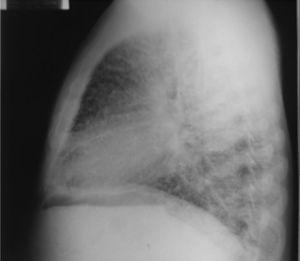

Radiografía de tórax lateral.

Figura 2.

(0,07MB).

Dentro de los exámenes diagnósticos se debe realizar, en primer lugar, una radiografía de tórax, que usualmente muestra calcificaciones micronodulares, bilaterales, opacidades reticulares lineales y uniformidad de tamaño de los microlitos distribuidos a lo largo de todo el árbol bronquial. Los anteriores hallazgos se han descrito como «tormenta de arena» (del inglés sandstorm)44 o «tormenta de nieve» (del inglés snowstorm)45, que predominan en las áreas basales y mediales del pulmón, con obliteración de los bordes cardiacos y diafragmáticos35.

Se observan depósitos en las superficies subpleurales, resultando en una opacidad lineal, que demarca las divisiones pulmonares y mediastinales46, conocida como línea negra pleural (del inglés black pleural line), la cual fue descrita por Felson, considerada como una ilusión visual secundaria a un área radiolucente que se da entre el parénquima pleural y las costillas45,47–50. Otros hallazgos típicos son pequeñas bulas apicales e imagen en panal de abejas, sin mención de compromiso de nódulos linfáticos51.